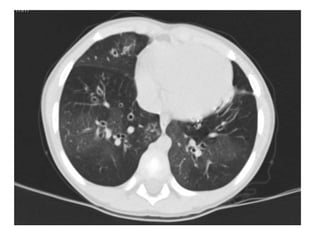

Alterações tomográficas em 250 crianças e adolescentes

Fischer GB et al. Paediatr Resp Rev. 2010;11:233-9

Alterações tomográficas em250 crianças e adolescentes Fischer GB et al. Paediatr Resp Rev. 2010;11:233-9

 Padrão de perfusão em mosaico e aprisionamento aéreo na

tomografia computadorizada de tórax;